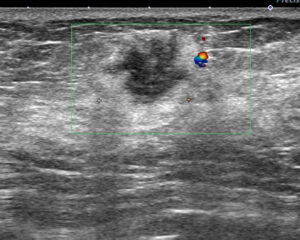

これも画像診断では、判断がつかない=小さいし、経過観察しましょう

と、されるケースでも私に「無駄な経過観察なし」なので

CELEROするので、「非浸潤がん」でした。